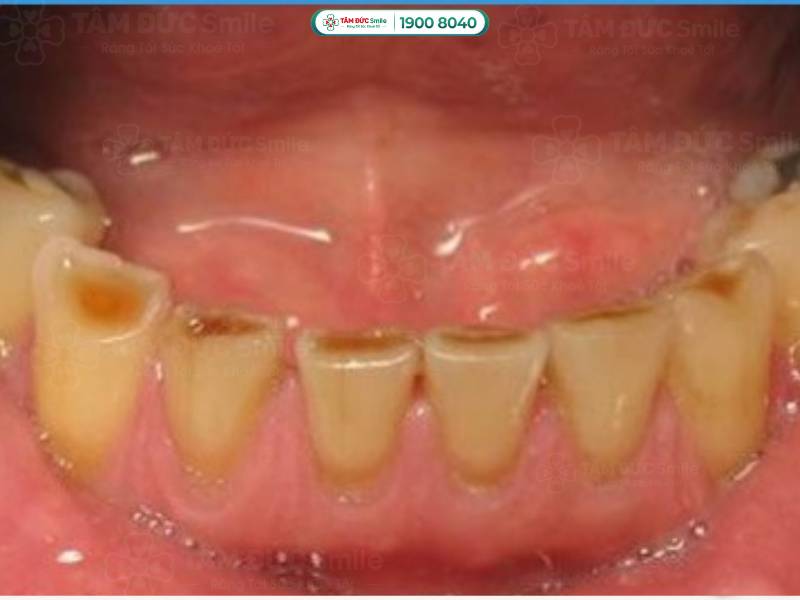

Răng bị mòn mặt nhai là hiện tượng lớp men răng ở phần trên cùng của răng bị bào mòn. Trên mặt nhai xuất hiện các vết lõm nông hoặc sâu không đồng đều, làm mất thẩm mỹ và ảnh hưởng chức năng răng miệng.

Răng bị mòn mặt nhai do mất mô răng. Lớp men răng bảo vệ không còn, cấu trúc của bề mặt nhai có sự thay đổi, bắt đầu xuất hiện các vết lõm. Tùy vào mức độ mòn men răng, vết lõm có thể nông hoặc sâu, làm bạn cảm thấy ê buốt khi ăn nhai.

Răng bị mòn mặt nhai là hiện tượng lớp men răng ở phần trên cùng của răng bị bào mòn